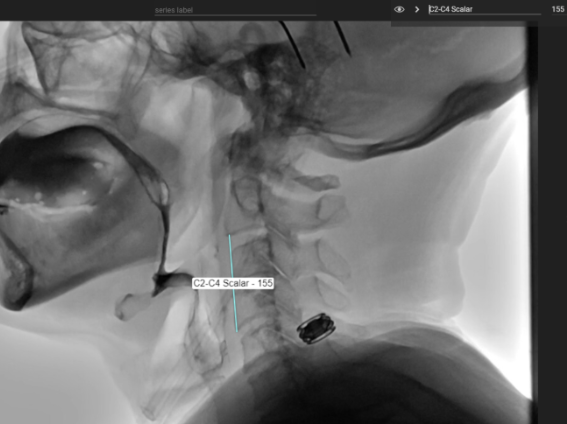

C2 - C4 Scalar

Quick Takeaways

Scaling measurements to the length of the C2–C4 cervical spine helps account for variability in overall body size, including differences related to sex and height (Molfenter & Steele, 2014).

For some measures, C2-C4 scalar may be used in place of external scalars.

Steps for Completion

Using the line tool, draw a line from the bottom corner of C2 to the bottom corner of C4.

Example: Use of freehand tool to label the spine and use of the line tool to create the C2-C4 scalar.